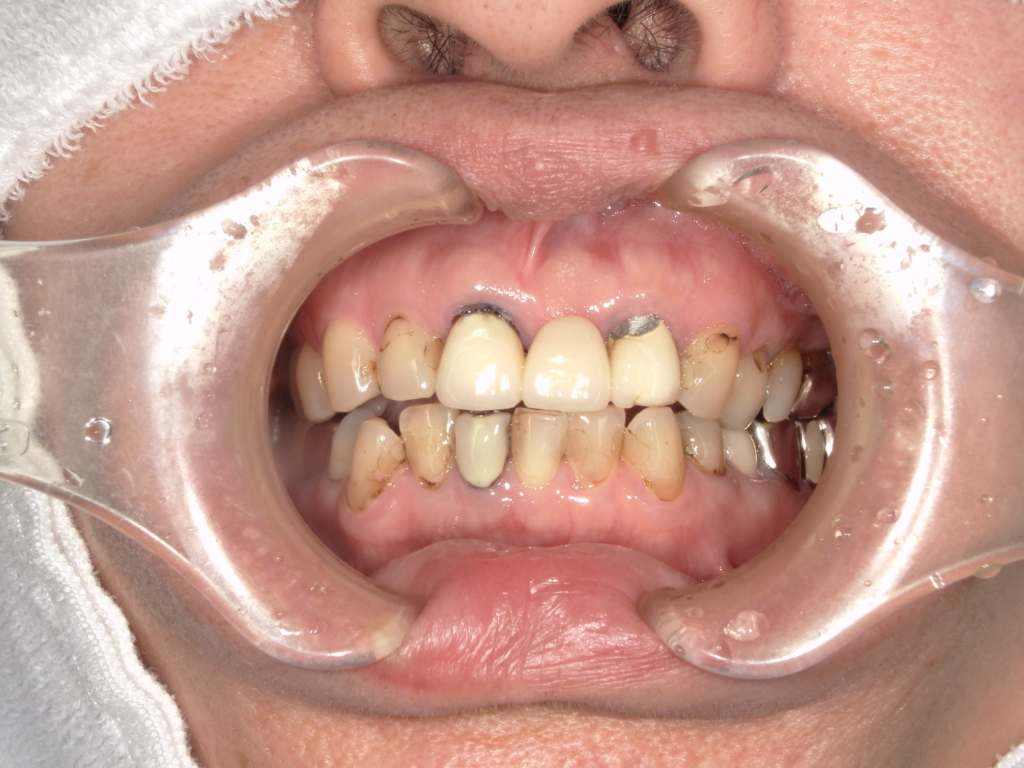

Y様インプラント実例 #44

左の上下の奥歯をインプラントで治療しています。

左下の奥歯は歯を抜くのと同時にインプラントの埋め込みを行っています。

被せものは上下、セラミックスで作っています。

治療前

治療後